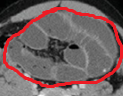

Red arrows — transition point. Multiple air-fluid levels (Courtesy Dr. V. Penopoulos)